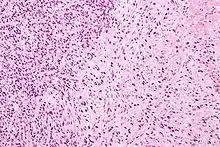

Gleason 4

Gleason pattern 4 glands are no longer single/separated glands like those seen in patterns 1-3. They look fused together, difficult to distinguish, with rare lumen formation vs Gleason 1-3 which usually all have open lumens (spaces) within the glands, or can be cribriform-(resembling the cribriform plate/similar to a sieve: an item with many perforations). Fused glands are chains, nests, or groups of glands that are no longer entirely separated by stroma-(connective tissue that normally separates individual glands in this case). Fused glands contain occasional stroma giving the appearance of "partial" separation of the glands. Due to this partial separation, fused glands sometimes have a scalloped (think looking at a slice of bread with bite taken out of it) appearance at their edges.[4][7]